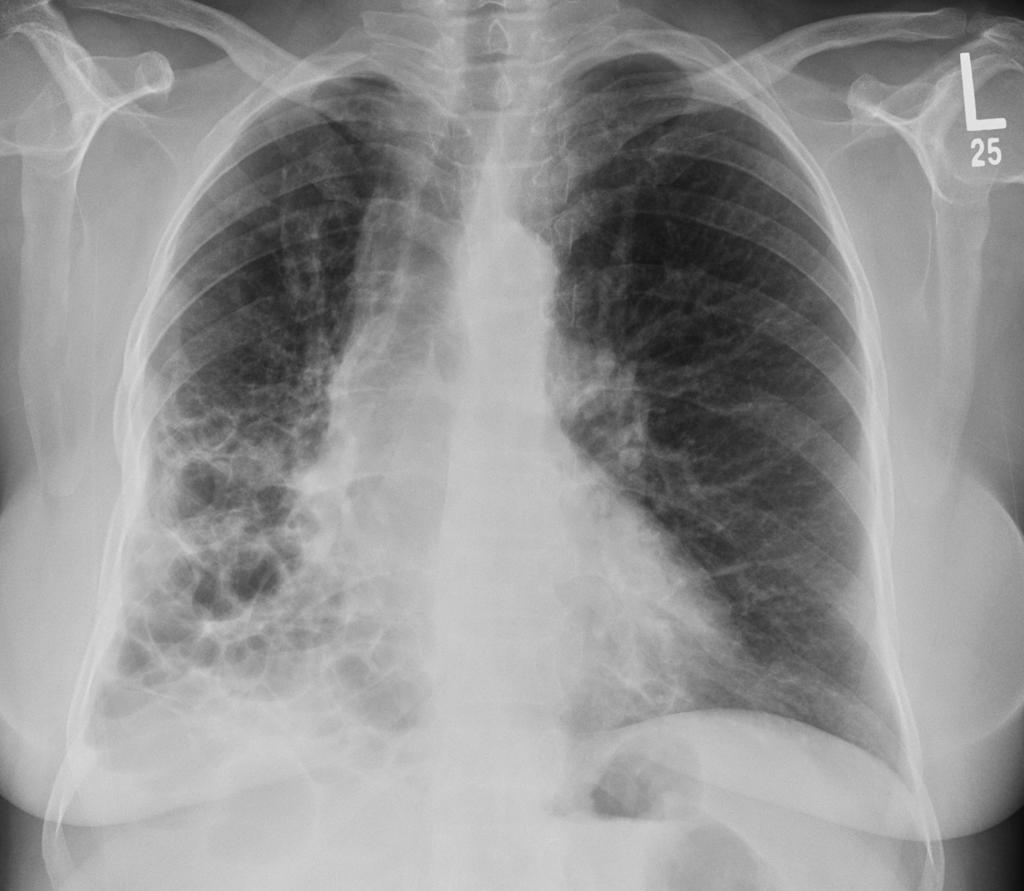

提到肺病,大多数人想到的可能是肺炎、肺癌这些"知名度"比较高的疾病,但有一类肺病却像个"隐形杀手",悄悄地损害着我们的肺部,它就是间质性肺疾病,简称ILD。 这个名字听起来就很专业,让人摸不着头脑,但实际上它离我们并不遥远。 据中华医学会呼吸病学分会统计,我国间质性肺疾病的患病率约为每10万人中有28-65人,而且这个数字还在逐年上升。 间质性肺疾病就像是肺部的"装修工人"出了问题,本来应该保持肺泡结构完整的间质组织开始"胡作非为",导致肺部纤维化、硬化,最终影响呼吸功能。 听起来有点可怕,但别慌,了解了它的"脾气",我们就能更好地应对。

肺泡周围有一层薄薄的间质组织,就像房子的墙壁一样,正常情况下它们井然有序,保证氧气和二氧化碳的正常交换

但当间质组织发生炎症、纤维化时,这堵""就变厚变硬了,气体交换就困难了

简单来说,间质性肺疾病是一大类累及肺间质的弥漫性肺部疾病的总称

这里的"间质"指的是肺泡壁、肺泡周围的结缔组织、毛细血管内皮细胞基底膜等结构

当这些部位发生炎症、纤维化时,就会影响肺部的气体交换功能